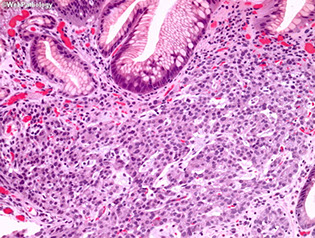

Figure 1: Gastric mucosal biopsies from children with autoimmune enteropathy often showed features of (a) chronic gastritis with increased lamina propria lymphoplasmacytic inflammation forming a superficial band within the mucous neck region. (b) In some cases, prominent intraepithelial lymphocytosis was identified within the surface, foveolar epithelium consistent with lymphocytic gastritis. (c) Concurrent autoimmune-related disorders were a common finding in patients with autoimmune enteropathy. Gastric biopsies taken from the fundus of case 14 demonstrated the features of autoimmune atrophic gastritis with partial parietal cell loss and superficial intestinal metaplasia. (d) In a subset of patients, multiple apoptotic bodies (arrows) were identified within the deep glandular mucosa.